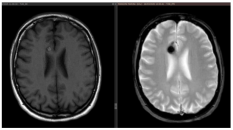

Figure 5.

(a). Axial, coronal, and sagittal GRE T2*-weighted MRI of a 79-year-old patient with severe cardiologic comorbidities and a progressive motor and sensory deficit of the right leg and foot, showing a left parasagittal CM with typical blooming artifact. (b). SRS treatment planning of the same patient for whom surgery was considered too risky.